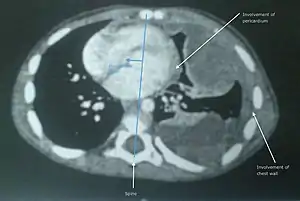

| Undifferentiated soft tissue sarcoma in left lung of young child | |